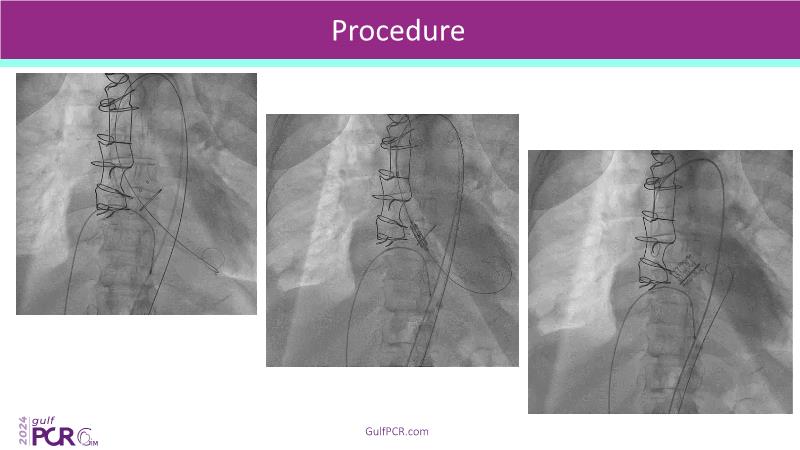

Stay ahead in TAVI innovation by exploring the advanced balloon-expandable Myval THV series. This session highlights the latest clinical data, optimal sizing and implantation techniques, and valuable real-world insights, including long-term follow-up results.

- To understand the best practices for Myval sizing and implantation technique for best outcomes